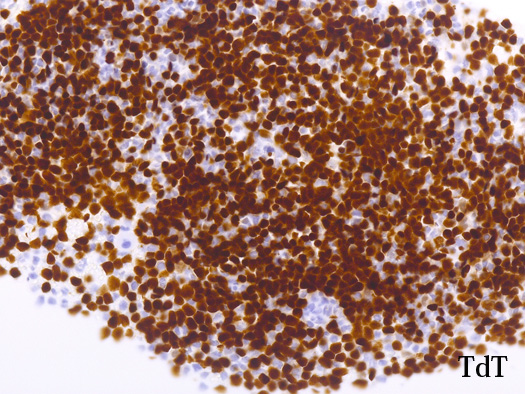

AULはcCD3、MPO、CD19、cCD22、およびCD79a発現を欠き, 通常1つの表面系統マーカー( CD13、CD33、またはCD7など)のみを発現する.CD38またはTdT発現を伴って, CD34およびHLA-DRが陽性になる. *2

blastic cellsは, CD45+, CD34+, CD38+, TdT+, CD7+, HLA-DR+, CD123+. cCD3-, sCD3-(FCM), CD20-, CD19-とCD79a-(?) (plasma cellが陽性でIHCでは判定が難しい), MPO-.